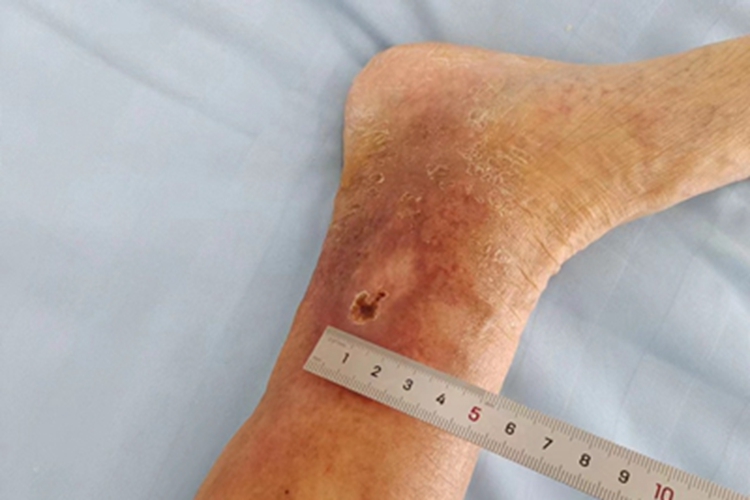

臁疮发作于患者小腿,可表现为一个脓疱形成近似圆形的小溃疡,可形成瘢痕结痂。

臁疮发作于患者小腿,可表现为一个脓疱形成近似圆形的小溃疡,几周后坏死的组织脱落,新的肉芽组织填充,可形成瘢痕结痂。